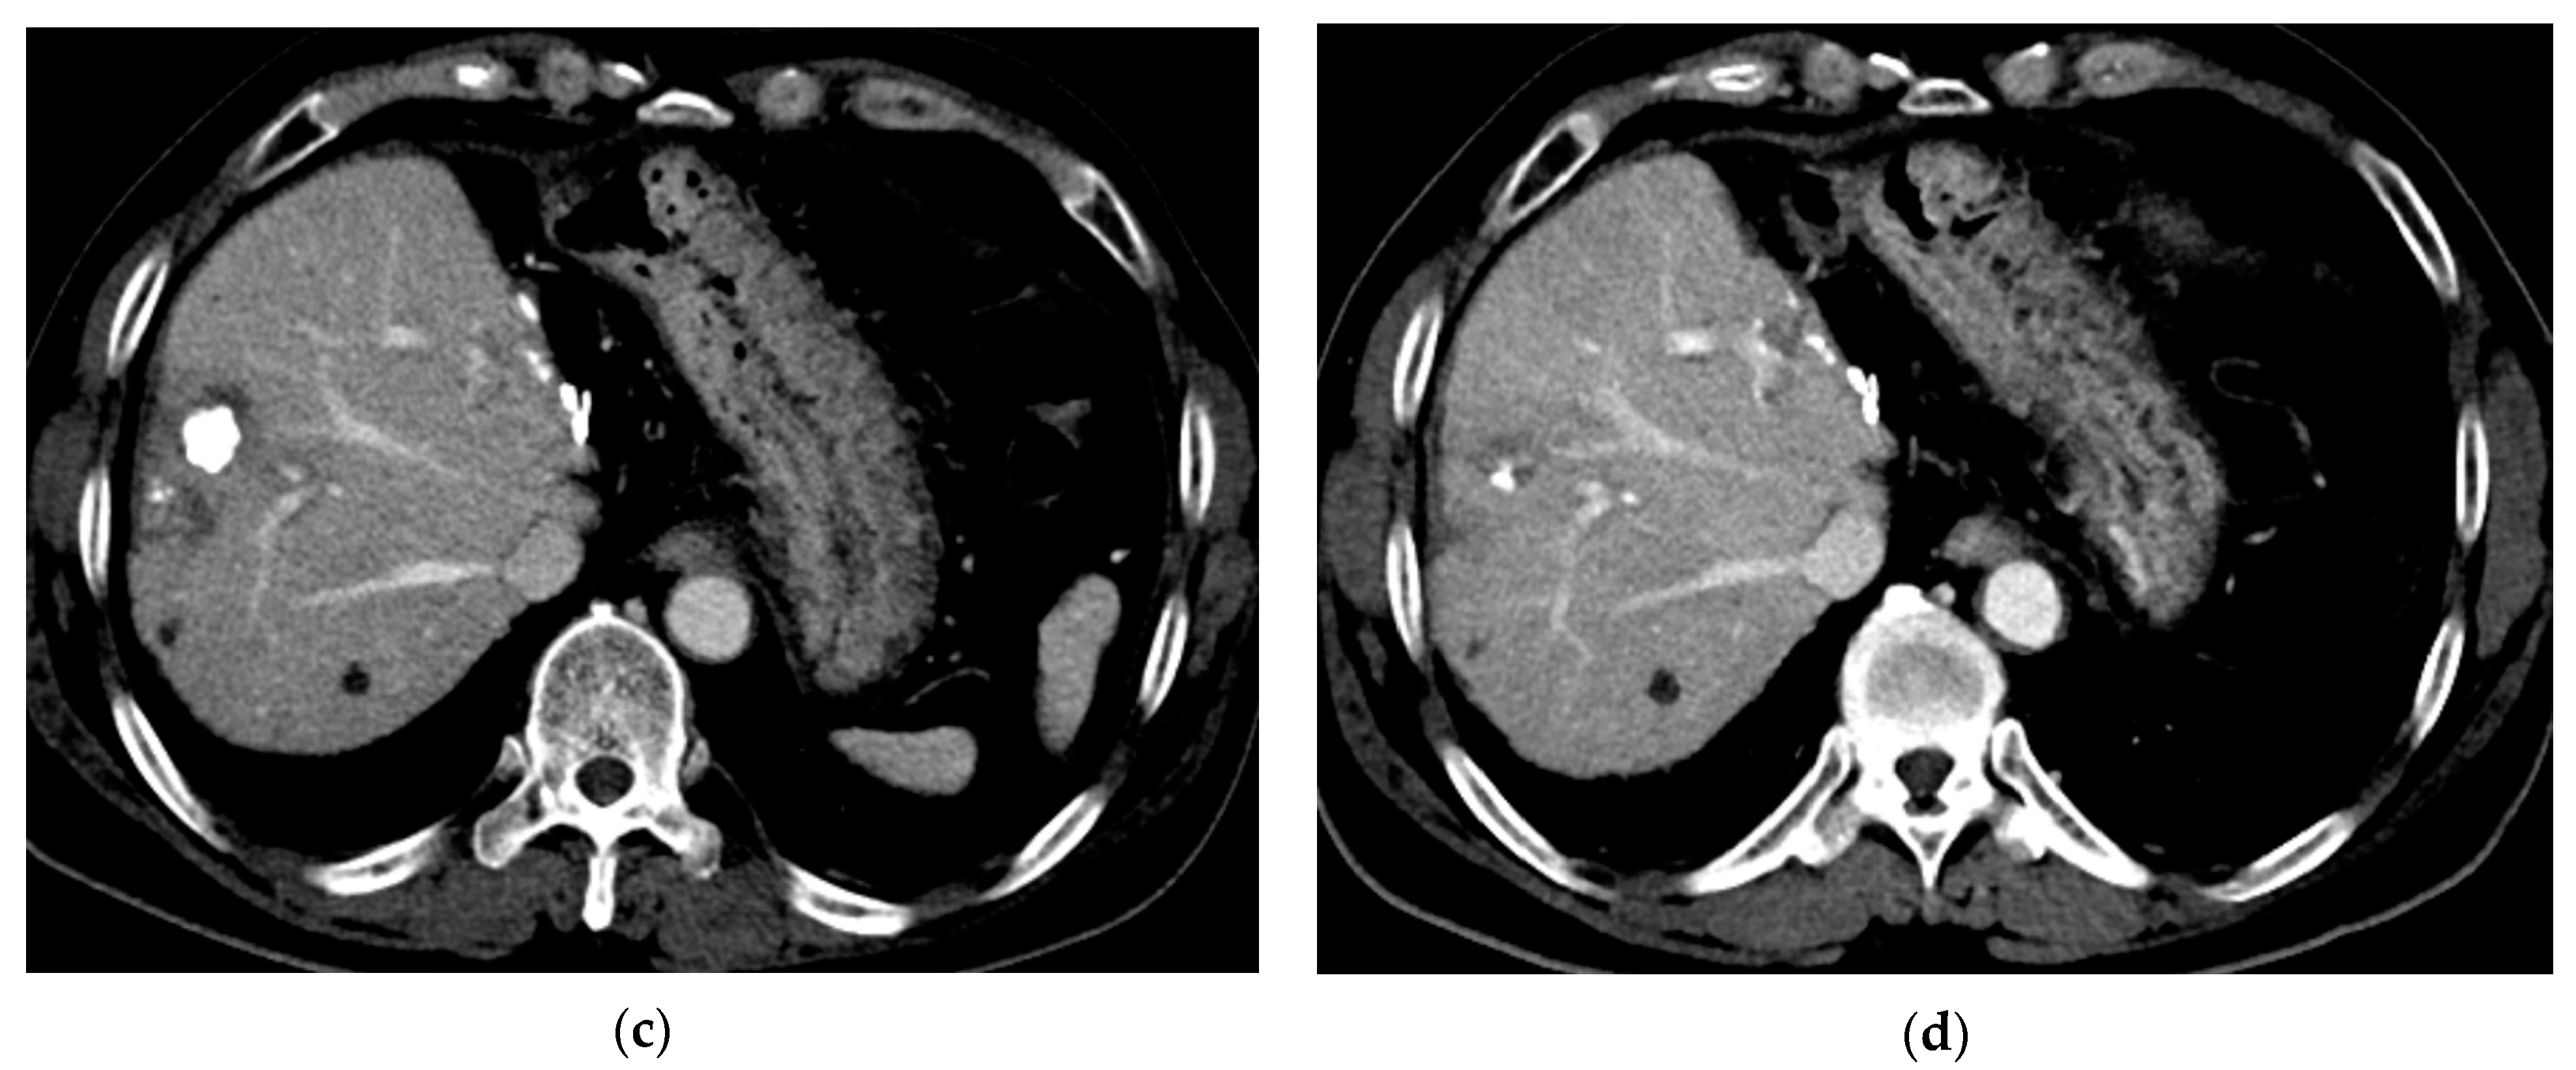

3.2. Follow-Up

3.3. Local Recurrence